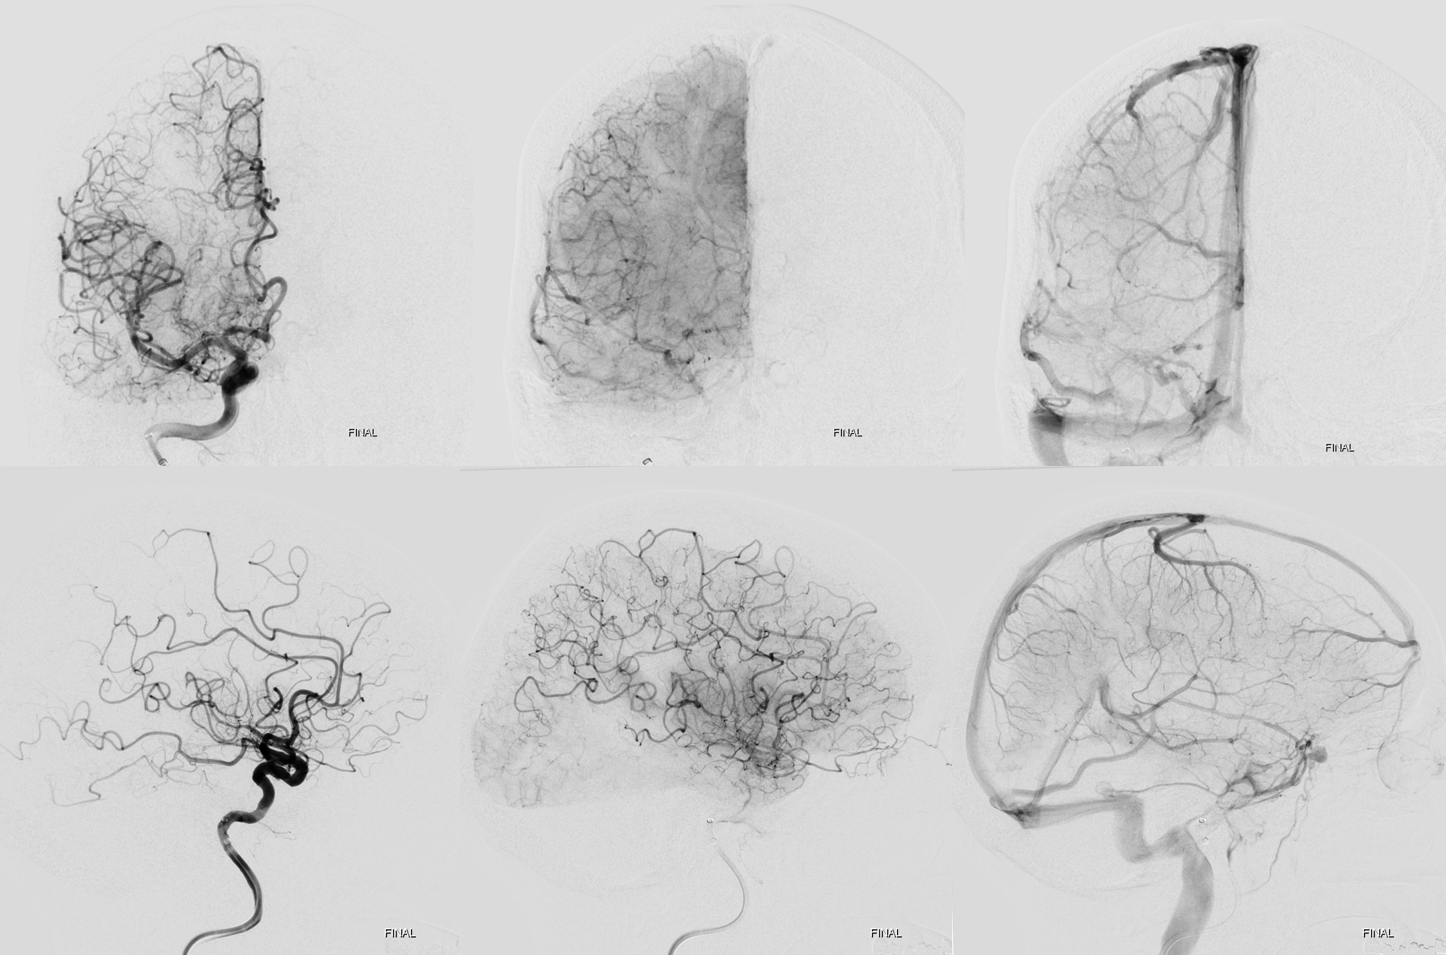

Thrombectomy

As predicted there is a second occlusion. See correlation between angios and DYNA

Distal (MEVO) thrombectomy

Post. There is still one branch from this area (dashed arrow) missing plus another one in the inferior division